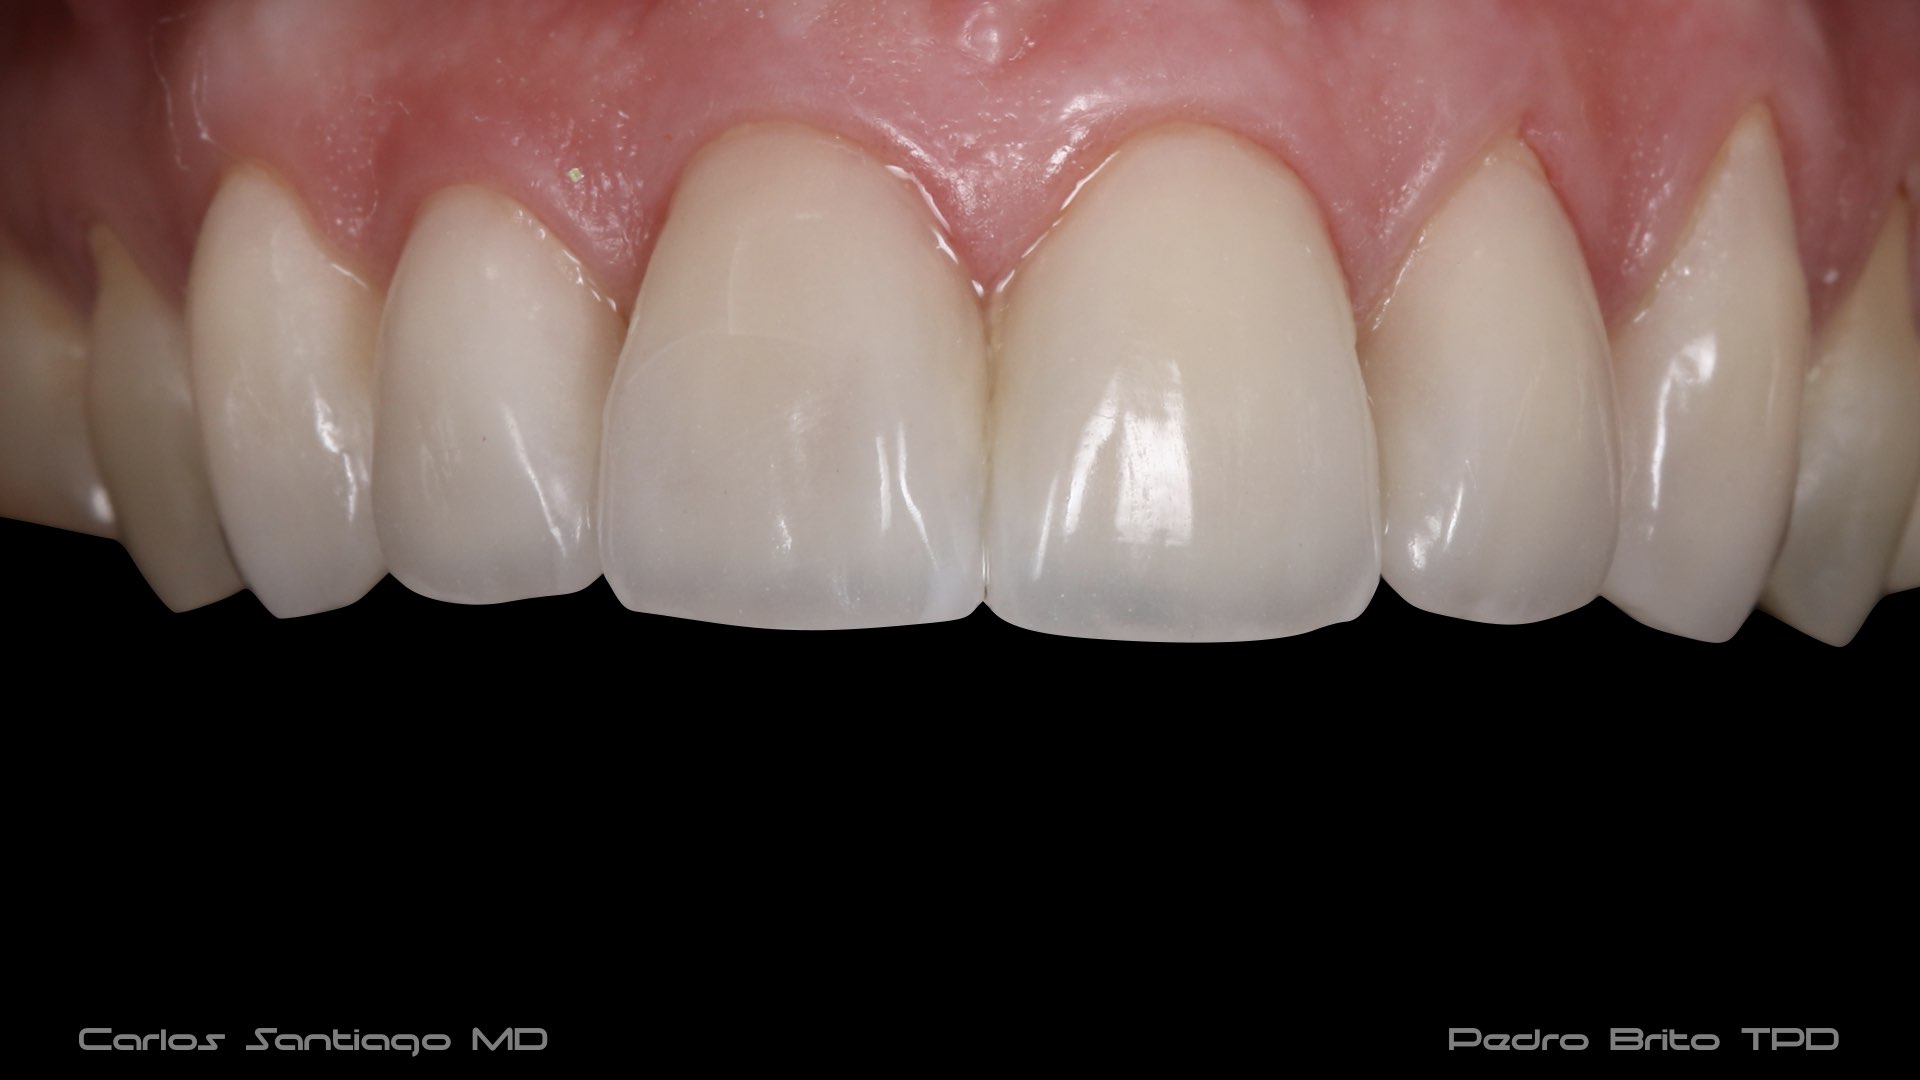

As Facetas Cerâmicas (lentes de contacto dentárias ou laminados), permitem corrigir da maneira mais estética e conservadora possível, problemas de forma e tamanho, côr e posição dos dentes, bem como substituir restaurações antigas e inestéticas.

São aderidas químicamente ao esmalte dentário de uma forma permanente, com o objectivo de melhorar a estética dos nossos pacientes.